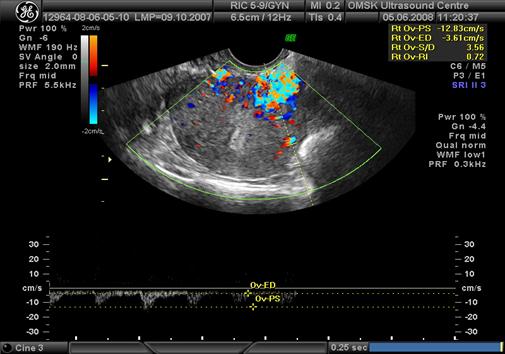

У 96 женщины основной и контрольной групп в доминантных миоматозных узлах проводилось исследование кровотока. При допплерометрии обнаружено два типа кровотока в миоматозных узлах у 69 пациенток основной группы: у 31,7% пациенток - нодулярный и у 68,3% - перинодулярный тип кровотока (рис.2, 3). В контрольной группе (27 пациенток) – точечный тип кровотока, независимо от размеров доминантных узлов. Для дальнейшего определения возможных патогенетических механизмов роста лейомиомы матки исследован индекс резистентности (ИР) в кровотоке доминантных узлов. Оказалось, что при лейомиомах с быстрым ростом узлов малых размеров по сравнению идентичными размерами узлов лейомиомы матки с медленным ростом узлов имеет место значительное превышение ИР - в 1,8 раза. Показатели ИР в доминантных узлах женщин основной группы нами были расценены как «пролиферативный» тип кровотока, определение которого, по нашему мнению, определяет подход к ведению пациентки независимо от размеров лейомиомы матки.

Рис.2 Нодулярный тип кровотока по данным УЗИ с допплерометрией